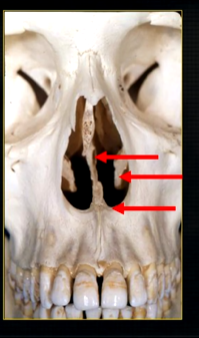

what is seen here?

the nasal septum and the inferior nasal concha

what is the bottom arrow showing?

the floor of the nose - just above the apices of the upper anterior teeth

more posteriorly - radiopacities indicate the nasal septum and floor of the nose

dense, thin , white line in the middle of the image is the nasal septum

less dense opacity is caused by the

inferior nasal concha

radiolucency - nasal septum

lateral wall of the nose